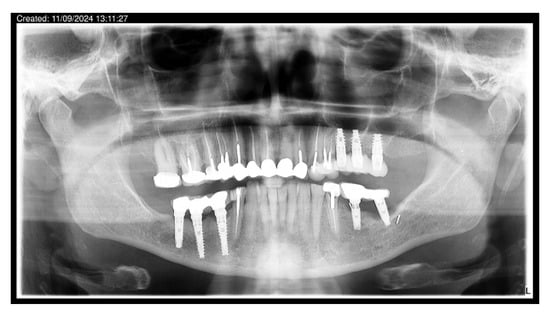

Patients were instructed on strict oral hygiene protocols and scheduled for periodic follow-up visits with their dentists and dental hygienists, as recommended by the clinical team. Long-term success was closely linked to adherence to these follow-up measures. Clinical and radiographic evaluations were conducted by the patients’ dentists and reported to the author. The patients included in this study were monitored for a follow-up period of 10–14 years. Examples include Patient No. 1 (14-year follow-up; Figure 8a) and Patient No. 5 (14-year follow-up; Figure 8b).

Figure 8.

(a) Patient No. 1; follow-up 14 years. (b) Patient No. 5; follow-up 14 years.